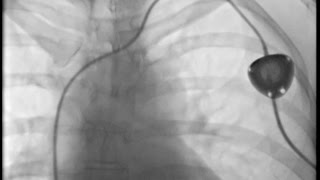

Port-A-Cath Installed This Morning!

Interventional Radiology - Portacath Device Insertion

Chest Port Placement